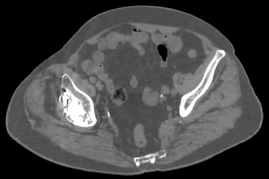

双侧髋关节置换术后(Smart MAR可以减少金属伪影)